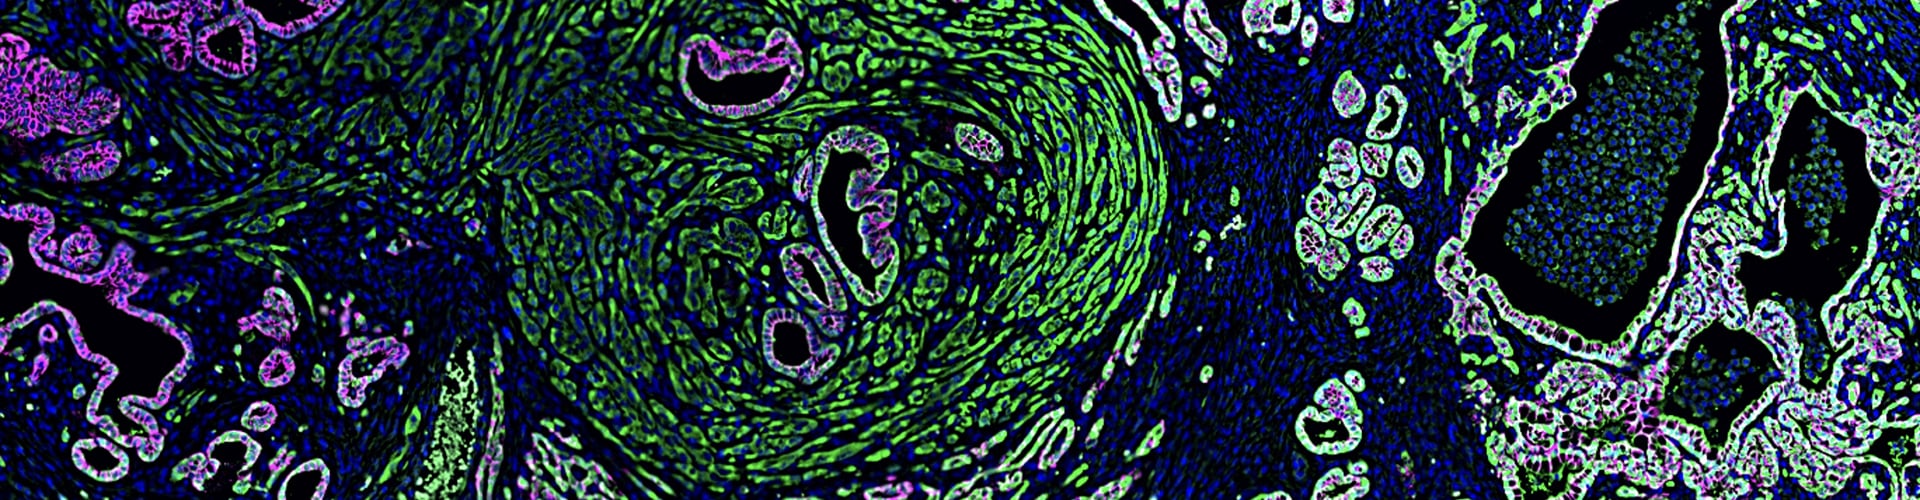

• Understanding mechanisms of cellular plasticity that facilitate metastasis

• Mechanism of epithelial-to-mesenchymal transition (EMT)

• Building novel genetically engineered mouse models to study epithelial plasticity and squamous/basal/quasimesenchymal subtypes in pancreatic cancer progression

• Reichert M, Bakir B, Moreira L, Pitarresi JR, Feldmann K, Simon L, Suzuki K, Maddipati R, Rhim AD, Schlitter AM, Kriegsmann M, Weichert W, Wirth M, Schuck K, Schneider G, Saur D, Reynolds AB, Klein-Szanto AJ, Pehlivanoglu B, Memis B, Adsay NV, Rustgi AK. Regulation of Epithelial Plasticity Determines Metastatic Organotropism in Pancreatic Cancer. Dev Cell. 2018 Jun 18;45(6):696-711.e8.